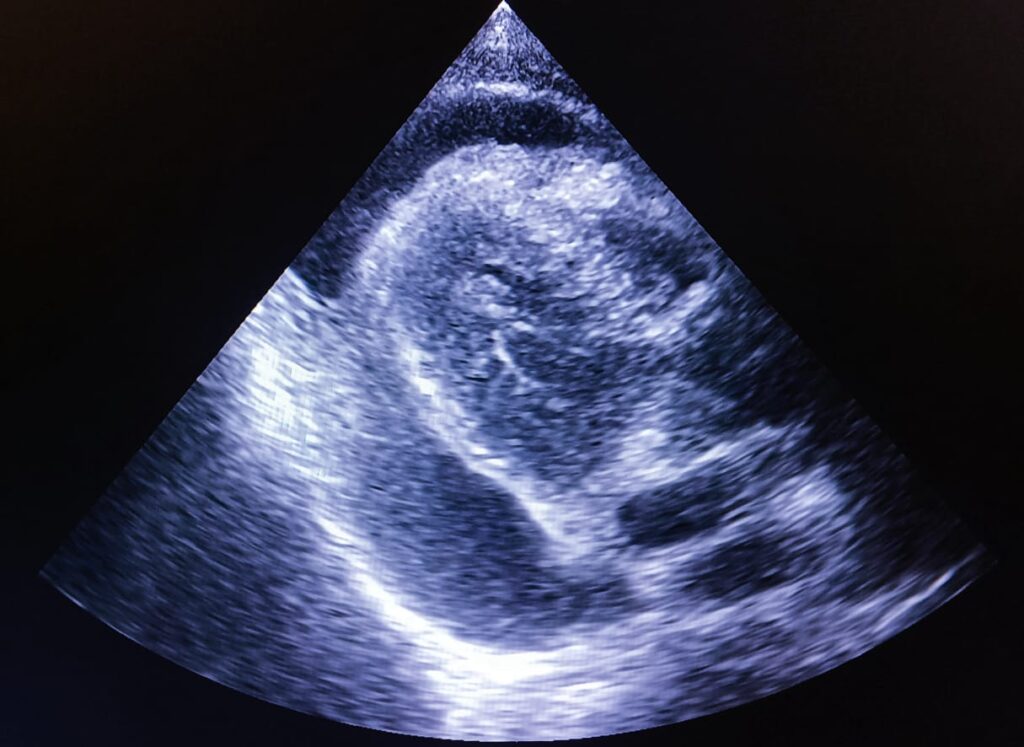

While scanning the left lobe of liver, glimpses of the heart from subxiphoid position prompted the experienced radiologist to look into the parasternal and apical views of the heart.

And there was moderate amount of pericardial effusion, a condition where the heart is surrounded with excess amount of fluid, that compresses the heart and hinders its normal pumping process. It may lead to cardiac tamponade, a serious life-threatening condition.